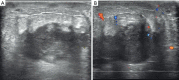

Results: In all, 7 cases (mean ± standard deviation age: 57.4±8.3 years; range, 49-70 years) were evaluated. The maximum size of breast lesions in 6 cases ranged from 1.2 to 4.5 cm, while 1 case showed a diffused pattern. Ultrasound features of breast metastases from lung cancer were irregular (5/7, 71.4%), indistinct (6/7, 85.7%), hypoechoic (7/7, 100.0%), and parallel (6/7, 85.7%) masses without calcification. Immunohistochemical staining test was positive for thyroid transcription factor 1 (TTF-1) in all patients (7/7, 100.0%), 3 cases (3/5, 60.0%) were negative for p63, 5 cases (5/5, 100.0%) were positive for cytokeratin 7 (CK7), 4 cases (4/5, 80.0%) were positive for napsin A.

Conclusions: The ultrasonographic features of lung metastases to the breast are clinically important to understand. A known history of the primary lung cancer is of great importance when evaluating patients with a breast nodule. The presence of an ipsilateral lung cancer, breast nodule and axillary lymphadenopathy should be considered with pathological and immunohistochemical data to differentiate breast metastases from a primary breast malignancy in this setting.